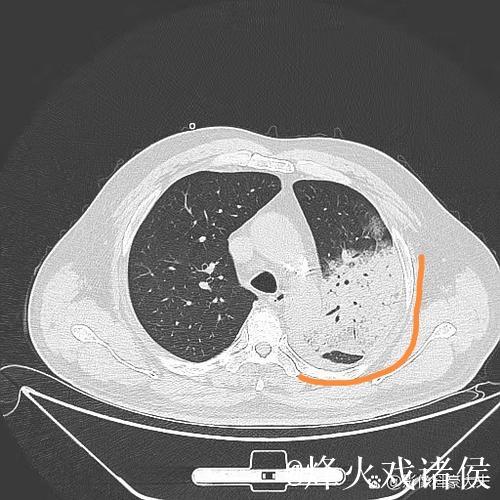

肺炎之所以让人恐惧,不仅因为它可能引发呼吸衰竭,甚至威胁生命,更因为它在短时间内剥夺了一个人对自己身体的信心。高烧、胸闷、呼吸困难,让人感到前所未有的无助。埃迪豪在住院期间,体验到那种“自己什么也做不了,只能依赖他人”的状态,这种深度依赖,让他对医护人员的信任不再停留在口头上,而是带着一种带有生死重量的感激。在无数次被抽血、做影像检查、调整药物方案的过程中,他感受到的是一种系统性的支撑机制从分诊、检查到治疗,再到随访,每一个环节都需要专业、协作和责任心。正是这种连贯的医护流程,让肺炎这样的急性疾病可以被及时识别和有效控制。

想象这样一个并不夸张的场景某个冬天的深夜,一位普通中年人因为持续高烧、咳嗽不止被家人紧急送往医院急诊。起初他以为只是普通感冒拖一拖就好,但胸闷和呼吸急促让他开始害怕。急诊医生为他安排了血常规、胸部影像检查,很快诊断出是肺炎并且已经出现肺部大片感染。值班的护士迅速为他建立静脉通路,挂上抗感染和补液的药物;呼吸科医生查看片子后,决定将他收入病房,密切监测血氧和生命体征。几天后,随着体温逐渐下降、咳嗽好转,他终于能平稳入睡。出院时,他握着主管医生的手说的一句“谢谢你们救了我”,背后是一整套完备的医疗体系在运转。这种经历,也正是很多人在重病之后才真正理解的现实只有当你真正被送进急诊室,才会明白一个反应迅速、配置合理、运行有序的医疗体系有多重要;只有当你在凌晨三点看到仍在查房的医生和整理病房的护士,才会明白医护人员的责任感远比外界想象更为沉重。